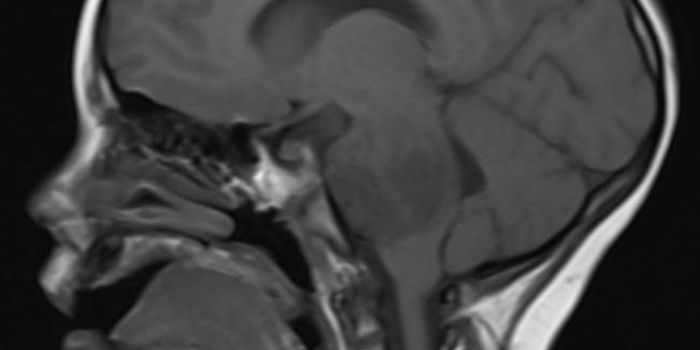

SEP 13, 2023Genetics & GenomicsA human brain organoid mosaic, created with a new tool called CHOOSE (CRISPR-human organoids-scRNA-seq) in this image - ...